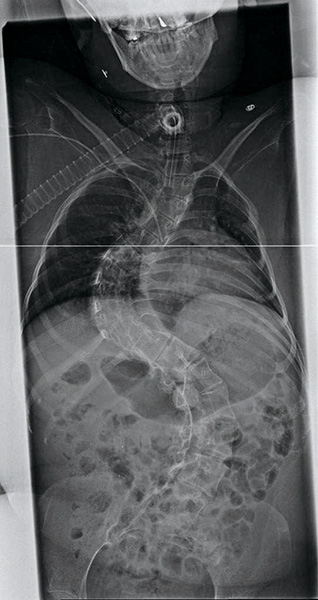

レントゲン写真

わたしの側湾は、胸椎から三つのカーブがあります。その中でも、腰椎カーブがほぼ90℃あり、とても座位がとれる体ではありません。ですが、V-trakを導入してパーツを組み合わせ、起こせるところは起こすことによって体幹に首が乗り、こんなに側弯がひどくても良い座位はとれるのです。もっともっとV-trakの性能を沢山のセラピストやユーザーさんに知ってもらって、快適な車いす生活を送って欲しいです。